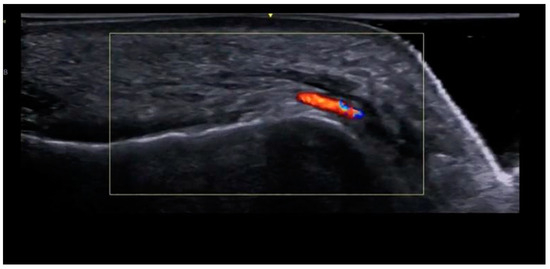

A small real-time ultrasound is common practice to find where arteries are for filler injections. This is not a guarantee at all though, this would just be good to see what areas are most populated with vessels, the likelihood of you using an ultrasound to accurately map out where all the vessels on your face are are close to zero.

This is an image from a Color Doppler ultrasound, these types of ultrasounds highlight bloodflow, meaning the red you see on the screen is a vein, artery or any vessel that carries blood.

(Red = blood is flowing towards the device, blue = blood is flowing away from it).

Buying these machines is expensive, usually $2k+ (at which point you can literally just get professional fat grafting). But thankfully you’re able to rent these kinds of machines online, I found a place local to me that rents it & lets me take it home for just a few hundred euros.

Personally I don't like ultrasounds for this as it gives you a false sense of security, but I need to include this as a safety measure incase some idiot uses this as a guide.

If you’re not financially able to afford an ultrasound (which I would not say is a worthwhile investment), then you can still rely on injection technique.

A small real-time ultrasound is common practice to find where arteries are for filler injections. This is not a guarantee at all though, this would just be good to see what areas are most populated with vessels, the likelihood of you using an ultrasound to accurately map out where all the vessels on your face are are close to zero.

This is an image from a Color Doppler ultrasound, these types of ultrasounds highlight bloodflow, meaning the red you see on the screen is a vein, artery or any vessel that carries blood.

(Red = blood is flowing towards the device, blue = blood is flowing away from it).

Buying these machines is expensive, usually $2k+ (at which point you can literally just get professional fat grafting). But thankfully you’re able to rent these kinds of machines online, I found a place local to me that rents it & lets me take it home for just a few hundred euros.

Personally I don't like ultrasounds for this as it gives you a false sense of security, but I need to include this as a safety measure incase some idiot uses this as a guide.

If you’re not financially able to afford an ultrasound (which I would not say is a worthwhile investment), then you can still rely on injection technique.